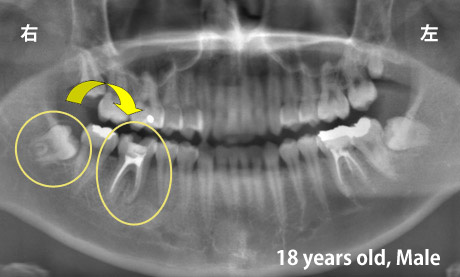

適切な条件がそろえば、歯の移植が可能です。歯の移植とは、治療することができない歯を抜いて、その場所へ本人の親知らずなどの歯を移す治療です。例えば、下のパノラマエックス線写真は18歳の男子です。右下の第一大臼歯が割れて痛みを伴って来院されました。この歯の保存できないと判断して、その歯を抜歯し,後ろにあるまだ生えていない親知らずをそこへ移植しました。移植の適切な条件とは、患者さん年齢が概ね40歳以下であること、口腔内に適切なドナー歯(主に親知らず)があること、移植歯(ドナー歯)と移植部位(受容側)の大きさが適合すること、などです。